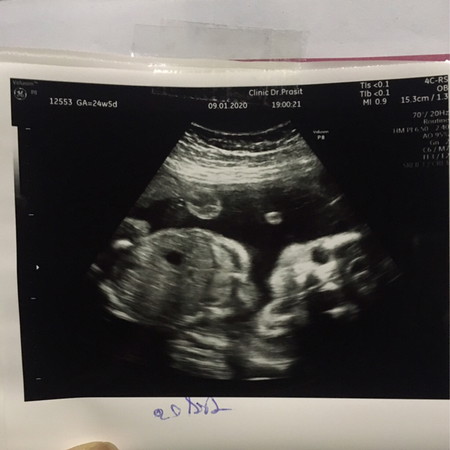

25+1 หมอบอกน้ำหนัก 740 กรัม น้อยรึมากอย่างใงค่ะ กังวน กลัวน้ำหนักต่ำ

VIP Parents25+1 หมอบอกน้ำหนัก 740 กรัม น้อยรึมากอย่างใงค่ะ กังวน กลัวน้ำหนักต่ำ